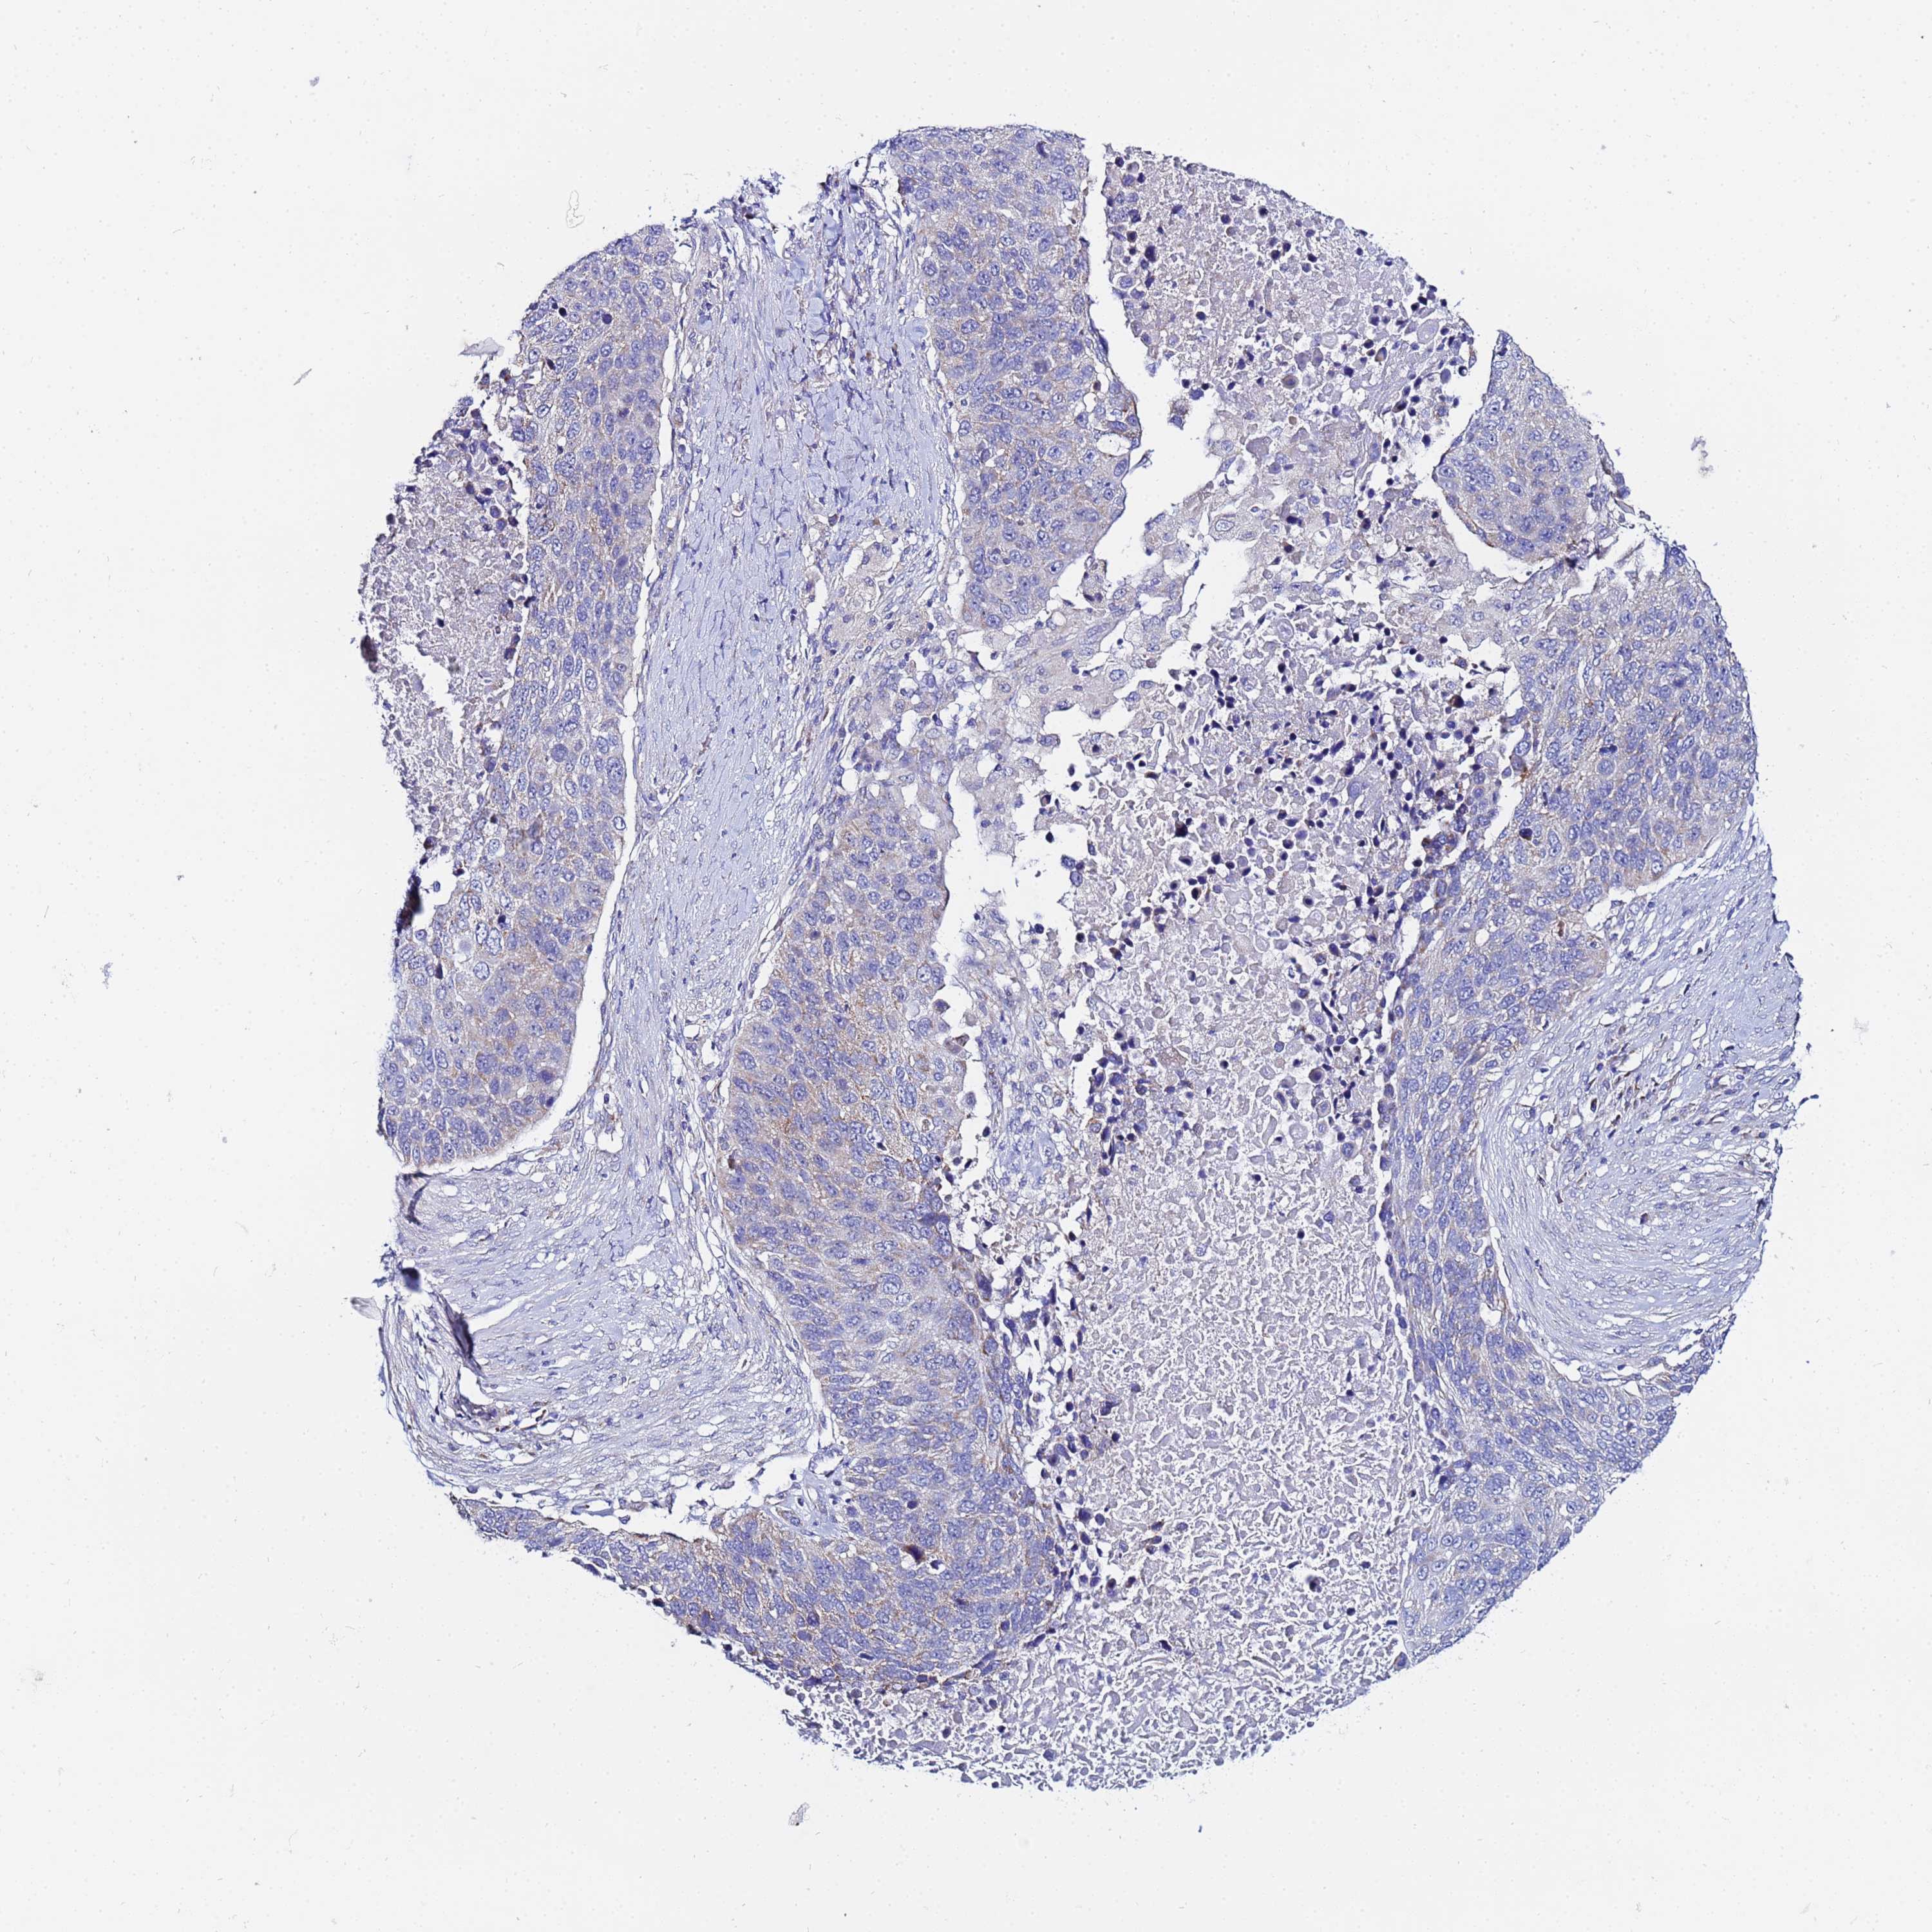

LUNG ADENOCARCINOMA (VALIDATION) - Interactive survival scatter ploti

The Survival Scatter plot shows the clinical status (i.e. dead or alive) for all individuals in the patient cohort, based on the same data that underlies the corresponding Kaplan-Meier plots. Patients that are alive at last time for follow-up are shown in blue and patients who have died during the study are shown in red.

The x-axis shows the expression levels (FPKM) of the investigated gene in the tumor tissue at the time of diagnosis. The y-axis shows the follow-up time after diagnosis (years). Both axes are complimented with kernel density curves demonstrating the data density over the axes. The top density plot shows the expression levels (FPKM) distribution among dead (red) and alive patients (blue). The right density plot shows the data density of the survived years of dead patients with high and low expression levels respectively, stratified using the cutoff indicated by the vertical dashed line through the Survival Scatter plot. This cutoff is automatically defined based on the FPKM cutoff that minimizes the p-score. The cutoff can be changed by dragging the vertical line or by entering a cutoff value in the square labeled "Current cut-off".

Under the Survival Scatter plot the p-score landscape (black curve; left axis) is shown together with dead median separation (red curve; right axis). Dead median separation is the difference in median mRNA expression between patients who have died with high and low expression, respectively. It is calculated as follows: median FPKM expression of dead patients with high expression - median FPKM expression of dead patients with low expression. This is intended to aid the user in visually exploring custom cutoffs and the associated p-scores and dead median separation.

Individual patient data is displayed and can be filtered by clicking on one or more of the category buttons on the top of the page. Categories describing expression level and patient information include: high, low, alive, dead, female, male and tumor stages. The scale of the x-axis can be toggled between linear and log-scale by clicking on the "x log" button. Mouse-over function shows TCGA ID, patient information and mRNA expression (FPKM) for each patient.

& Survival analysisi

Kaplan-Meier plots summarize results from analysis of correlation between mRNA expression level and patient survival. Patients were divided based on level of expression into one of the two groups "low" (under cut off) or "high" (over cut off). X-axis shows time for survival (years) and y-axis shows the probability of survival, where 1.0 corresponds to 100 percent.

FAHD2A is not prognostic in Lung Adenocarcinoma (validation)

: 19.09

P scorei

N/A

Average pTPM 16.7

Number of samples 105